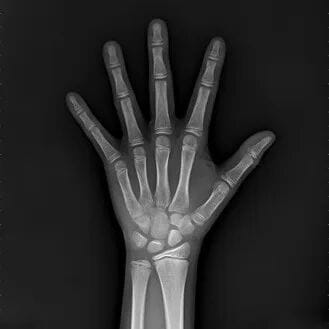

本次专场中,借助专业的骨龄检测设备,通过拍摄孩子左手腕部的X光片,来科学解读其骨骼的成熟状况。

·骨龄>年龄:可能提示发育提前,剩余的生长时间可能相对缩短。

·骨龄<年龄:可能属于“晚长型”,但也需要排除其他生长缓慢的原因。

·骨龄≈年龄:说明生长发育节奏基本同步。

骨龄就像孩子的“生长余额提醒”,它能帮助我们更科学地判断,孩子的生长空间还有多少,目前的节奏是否需要调整。